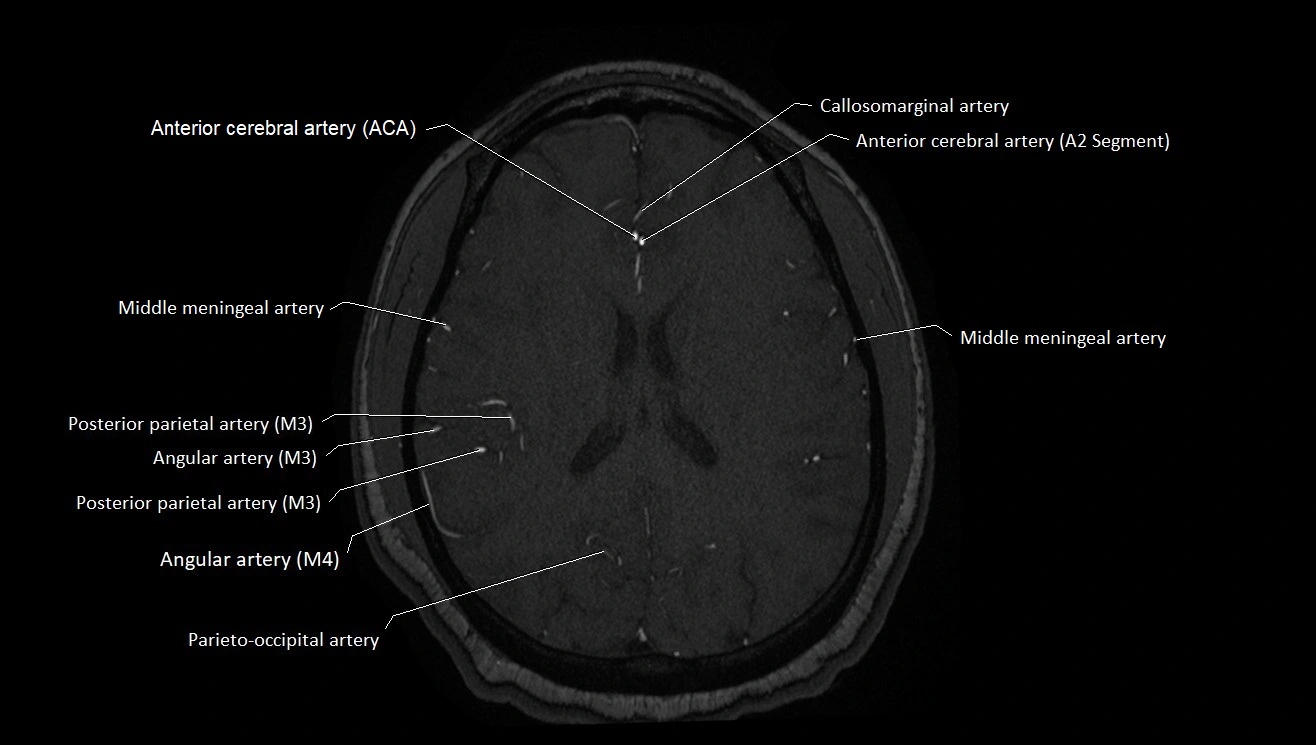

MRA (Magnetic Resonance Angiography):

• Flow-related enhancement makes the AChA appear as a bright, linear vascular signal against suppressed background

• High sensitivity for origin and proximal course; distal branches may be too small to resolve

• Detects stenosis, occlusion, aneurysm, AVM feeders